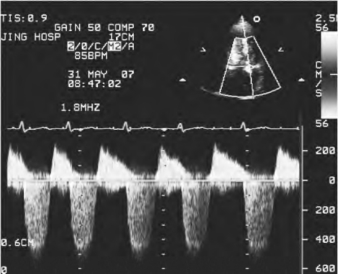

图13-9 二尖瓣反流连续型多普勒频谱图

收缩期负向高速反流频谱

①异常高速血流频谱:连续波多普勒取样线于彩色反流束处取样,可记录到收缩期负向单峰高速血流频谱,反流速度多数≥4m/s(图13-9),反流压差≥8.53kPa(64mmHg)。

②反流频谱灰度:轻度反流时,频谱灰度暗淡;重度反流时,频谱灰度强,高速区灰度最亮。